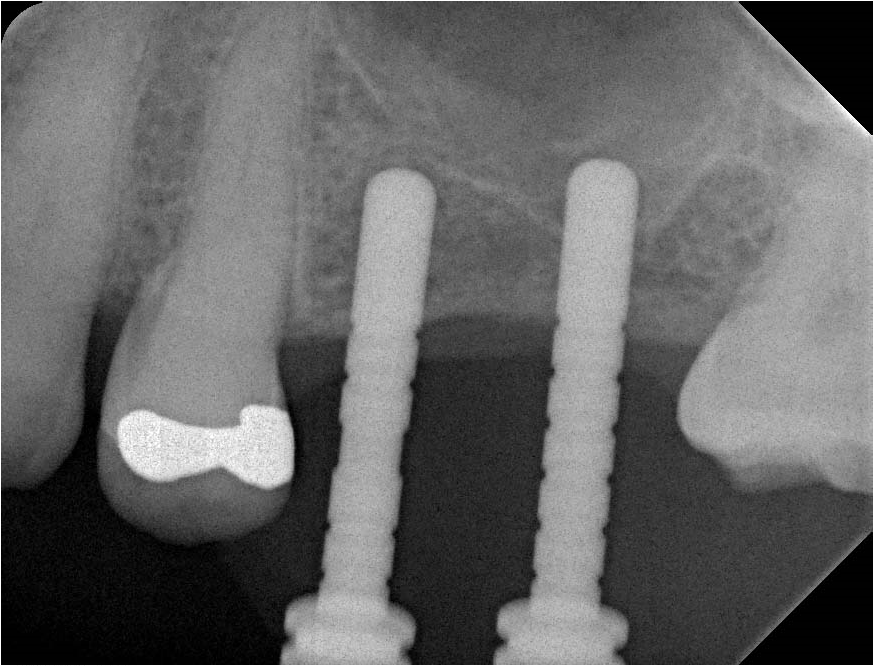

Two 4.1mm and 4.8mm tissue level implants were then placed, achieving primary stability of around 20 Ncm. The surgical site was then carefully closed and left to heal for four months.

Four month review radiograph showed excellent consolidation of the sinus floor graft, and ISQ readings of over 70 confirmed integration of the implants.